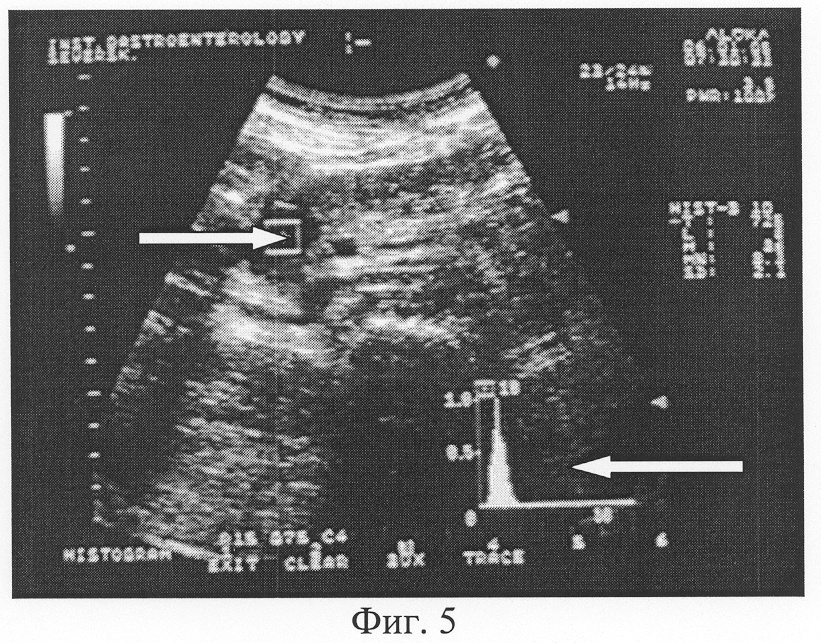

Способ-прототип несет в известной степени элемент субъективизма при оценке характера содержимого двенадцатиперстной кишки, требует определенной наработки, опыта в проведении заключения по характеру содержимого ДПК. Это и вызвало необходимость разработки и внедрения нами предлагаемого способа ультразвуковой оценки содержимого кишки с использованием гистографии. Характеристика полученной гистограммы проводится по двум показателям: «преобладающей» эхоинтенсивности MN и оценке графической кривой гистограммы. Построенная гистограмма исследуемого очерченного участка содержимого ДПК оценивает в конкретных цифрах показатель «преобладающей» эхоинтенсивности MN исследуемой зоны (Фиг.3-6). Чем выше значение MN, тем больше плотность среды. По виду распределения на гистограмме и по показателю, соответствующему количеству пикселей с «преобладающей» эхоинтенсивностью, проводят оценку эхогенности и степени неоднородности содержимого двенадцатиперстной кишки в конкретных единицах величины MN. Распределение эхоинтенсивности при графической гистографии проводится в виде построения аппаратом ультразвуковой диагностики своеобразной графической кривой (Фиг.3-6). Если гистограмма имеет вид явно выраженного высокого острого пика в графическом ее изображении, то очерченный участок изображения соответствует однородной среде, что является нормальным показателем при оценке содержимого ДПК после приема жидкости натощак. Кроме этого, чем выше число пикселей с данной эхоинтенсивностью, тем графический пик более острый и высокий с относительно узким «столиком» основания графической кривой – значит среда более однородна (Фиг.3-5). Графическое распределение в виде «столика» с относительно широким основанием и несколькими пиками означает неоднородность среды, что свидетельствует о нарушении моторно-эвакуаторной способности верхних отделов желудочно-кишечного тракта (Фиг.6).

В результате проведенного исследования 237 пациентов нами определен норматив значения показателя «преобладающей» эхоинтенсивности MN содержимого двенадцатиперстной кишки в выделенном участке изображения, равный 8-12 единицам. В случае снижения этого показателя считаем правомочным определить содержимое желудка как – «эхогенность содержимого двенадцатиперстной кишки снижена» (Фиг.5). Эти ультразвуковые параметры будут характерны для задержки эвакуации содержимого из двенадцатиперстной кишки. В случае превышения данных значений MN показатели эхогенности содержимого ДПК будут главным образом указывать на снижение измельчающей функции желудка, ускорение эвакуации содержимого из желудка в двенадцатиперстную кишку (Фиг.3, 6).

Фиг.5. Трансабдоминальное ультразвуковое исследование двенадцатиперстной кишки. Гистографический анализ содержимого ДПК с использованием зоны маркера в виде фиксированного квадрата с заранее заданной величиной в 1 см2 (обозначен стрелкой ). Значение показателя преобладающей эхоинтенсивности MN содержимого двенадцатиперстной кишки составило 6,4 единицы (норматив 8-12 единиц). Острый пик графической кривой гистограммы (обозначен стрелкой ) подтверждает факт однородного содержимого.